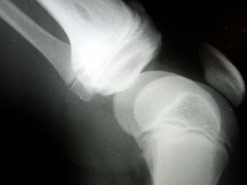

Osteoporosis

One in two women and one in five men in the UK over the age of 50 will break a bone because of osteoporosis.

Losing bone density is a natural part of the ageing process but what makes some people more susceptible to porous bones than others?

Being post-menopausal, taking certain prescription drugs, smoking and drinking are all risk factors for developing osteoporosis.

In this week’s Check Up Barbara Myers is joined by Dr Nicola Peel, consultant in metabolic bone medicine to take your questions on bone health and osteoporosis.